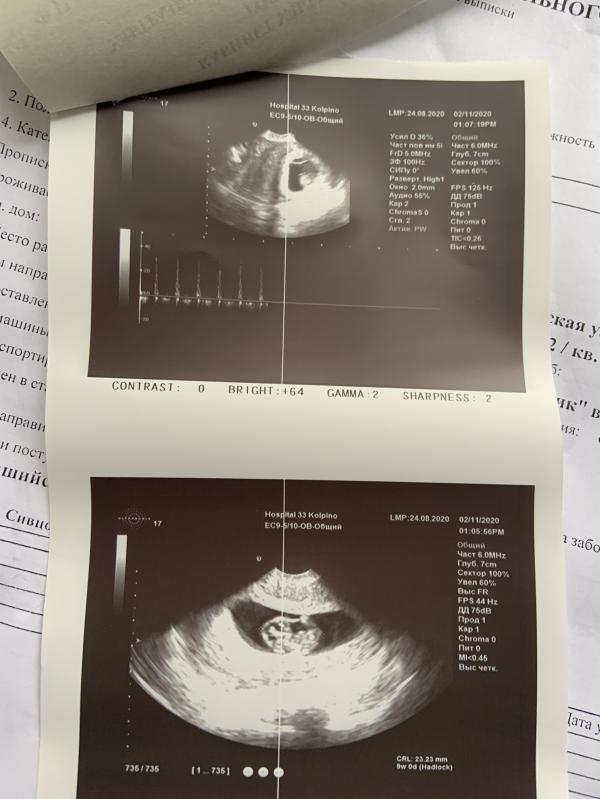

Девочки, всем привет! Сегодня утром резко открылось кровотечение, срок 9 недель

Приехала в больницу, сделали УЗИ, с ребеночком все хорошо, сердечко бьется. Вкололи ношпу и кровоостанавливающие. Сказали пить утрожестан, капельниц никаких не надо. От чего такое возможно? Я не нервничала, наоборот дома последнюю неделю была, отдыхала. Было ли у вас такое?